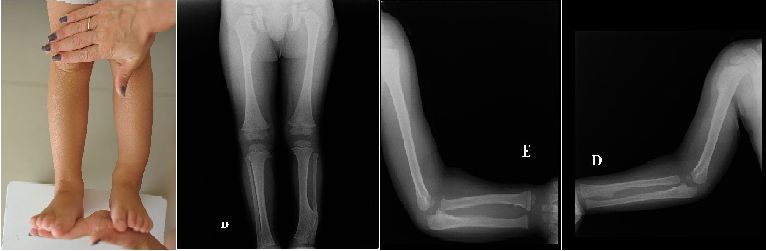

Ребенку 2 года 8 месяцев. Около полугода назад появилась деформация нижней трети левой голени. Сделали рентгенограммы. У матери ребенка так же экзостозы в верхней трети большеберцовой кости, ребер.Что можно предпринять при такой деформации голени?

У ребенка имеется полиоссальная форма экзостозной хондродисплазии, которая лечиться последовательным удалением экзостозов путем краевой резекции. Какие-либо коррегирующие операции в данном возрасте не показаны.